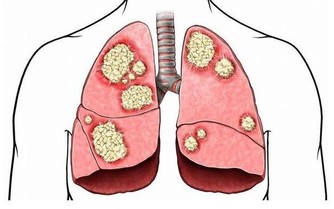

肺癌是“癌症之王”,是人類死亡的頭號殺手。肺癌的發病率男性多於女性,城市多於農村。

肺癌不是吸煙一族的專利,這些致病因素更可怕

肺癌並非吸煙一族的專利,經常接觸二手煙、做飯的女性也是肺癌的高危人群。肺癌的致病因素比較複雜,空氣污染、環境因素、粉塵、刺激性氣味環境、遺傳史等等都是導致肺癌的致命因素,它就像一種慢性病一樣,在某種致病因素的長期刺激下,正常細胞會發生癌變,慢慢地形成腫瘤。據了解,閆懷禮在河北涿州拍攝一部叫《俏羅城》的電視劇。當地的蒼蠅、蚊子特別多,當時有一場戲拍戲的現場噴灑了很多敵敵畏,很多人都因為濃重的味道離開了,當時閆懷禮嗅覺不好感覺不到,長時間處在敵敵畏濃重的環境裡面,拍戲空擋還在那裡休息,好友六小齡童分析這是他患病的誘因之一,再加上多年拍戲工作太過勞累,閆懷禮才患上了肺癌。

據肺癌幫APP病例庫統計,小細胞肺癌約佔10%。小細胞肺癌,其癌細胞生長的速度快,轉移也迅速,且容易有抗藥性,大多為吸煙所引起,也與環境或基因有關。

肺腺癌約佔50%,以女性為主。肺腺癌為最常見的肺癌,也是不吸煙者(多數為女性的45歲以下)常見的類型,容易遠端轉移是其特徵。治療的原則得根據期別,通常一、二期可經由評估後進行手術,之後再做化療等。

3、鱗狀上皮細胞癌:早期多為局部向外延伸的轉移

4、大細胞肺癌:生長速度快,預後不佳

患者人數約佔肺癌的5%,生長速度較快,會迅速經由血路及淋巴擴散,預後不佳。